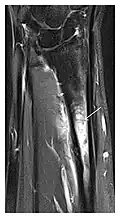

-

a -

b -

c

Figure 8: Proximal diaphyseal fatigue fracture of the tibia in a 20-year-old man with a history of regular jogging. (a) Lateral radiograph shows no obvious fracture lines but a subtle localized medial tibial cortex periosteal reaction (arrows). (b) Sagittal reformatted CT image acquired 1-month after the radiograph shows a linear hypoattenuation in the tibial cortex (arrowhead), as well as obvious periosteal thickening (arrows). (c) Sagittal T2-weighted fat-saturated image acquired the same day shows an area of hyperintensity spreading over the proximal tibia (arrows), which is consistent with the presence of proximal tibial fracture.[1]